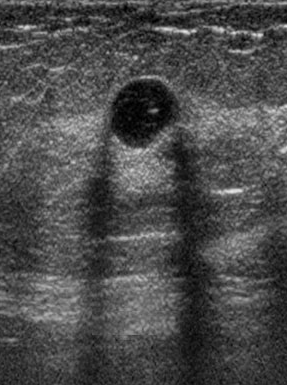

The target dataset was developed from 35 breast ultrasound scans that were segmented by an image-processing expert with extensive experience in breast lesion segmentation (the second author). The images, collected from the Web, are of different dimensions, ranging from to pixels (Figure 3, images resized for sake of illustration). These are the same images used to introduce EFIS originally [1].

Ultrasound images are generally difficult to segment, primarily due to the presence of speckle noise and low level of local contrast. It should be noted that the segmentation of ultrasound actually does require a complete processing chain, (including proper preprocessing and post-processing steps). However, the purpose of using these images was solely to demonstrate that the accuracy of the segmentation can be increased with the application of SC-EFIS.